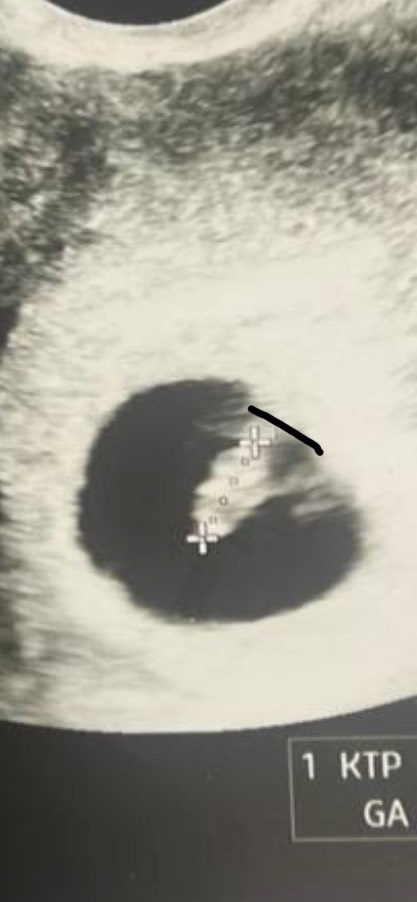

Девочки , я конечно возможно цепляюсь уже за свои фантазии , но ктр замерили верно ? Как будто эмбрион не полностью замерили ?

Ну вот она внизу а то что выше ? Почему то думала это голова 😕